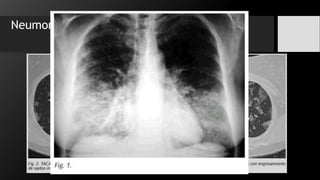

Neumonía

La neumonía en rx se manifiesta con una imagen típica de patrón alveolar y broncograma

aéreo, con distribución segmentaria, lobar o difusa, además de cambios intersticiales difusos.

Neumonía Lobar

• Streptococcus Pneumonae.

• Cisuras interlobares bien definidas.

• Signo de la silueta.

• Broncograma aéreo.

Neumonía La neumonía enrx se manifiesta con una imagen típica de patrón alveolar y broncograma aéreo, con distribución segmentaria, lobar o difusa, además de cambios intersticiales difusos. -Bacteriana -Viral -Micótica -Parasitaria Patrones de la neumonía Lobar Segmentaria Intersticial Redondo Cavitario

Neumonía Lobar • StreptococcusPneumonae. • Cisuras interlobares bien definidas. • Signo de la silueta. • Broncograma aéreo.